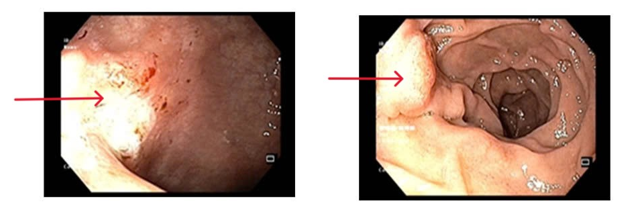

- Nội soi dạ dày: Niêm mạc hang vị phù nề xung huyết, rải rác có vài trợt nông và có hình ảnh viêm teo niêm mạc dạ dày (C2), bờ teo lan qua góc bờ cong nhỏ. Mặt trước hang vị có ổ loét kích thước ~ 0.8cm, bờ phù nề, đáy phủ giả mạc trắng

Hình 1: Hình ảnh nội soi dạ dày có tổn thương phù nề xung huyết tại niêm mạc hang vị (bên trái) và ổ loét ở mặt trước hang vị (bên phải)